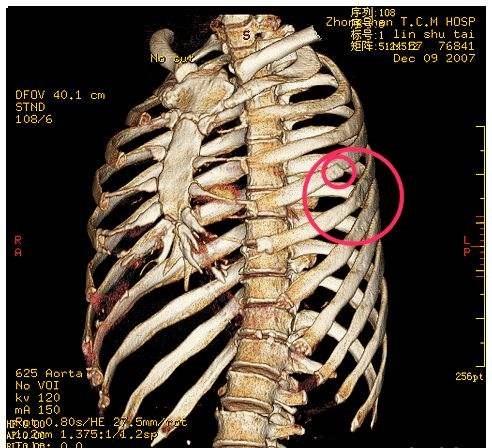

(4)肋骨和脊柱

胸部CT骨骼,包括肋骨和胸椎。可以看看肋骨,有没有肋骨骨折,肋骨上面有没有长东西,例如肋软骨瘤等等。还可以观察脊柱,胸椎有没有毛病,有没有胸椎骨折,占位,肿瘤,神经有没有受压等等。

肋骨骨折